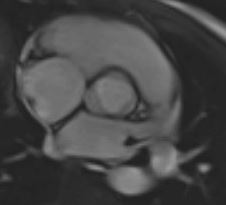

Aortic Root Series